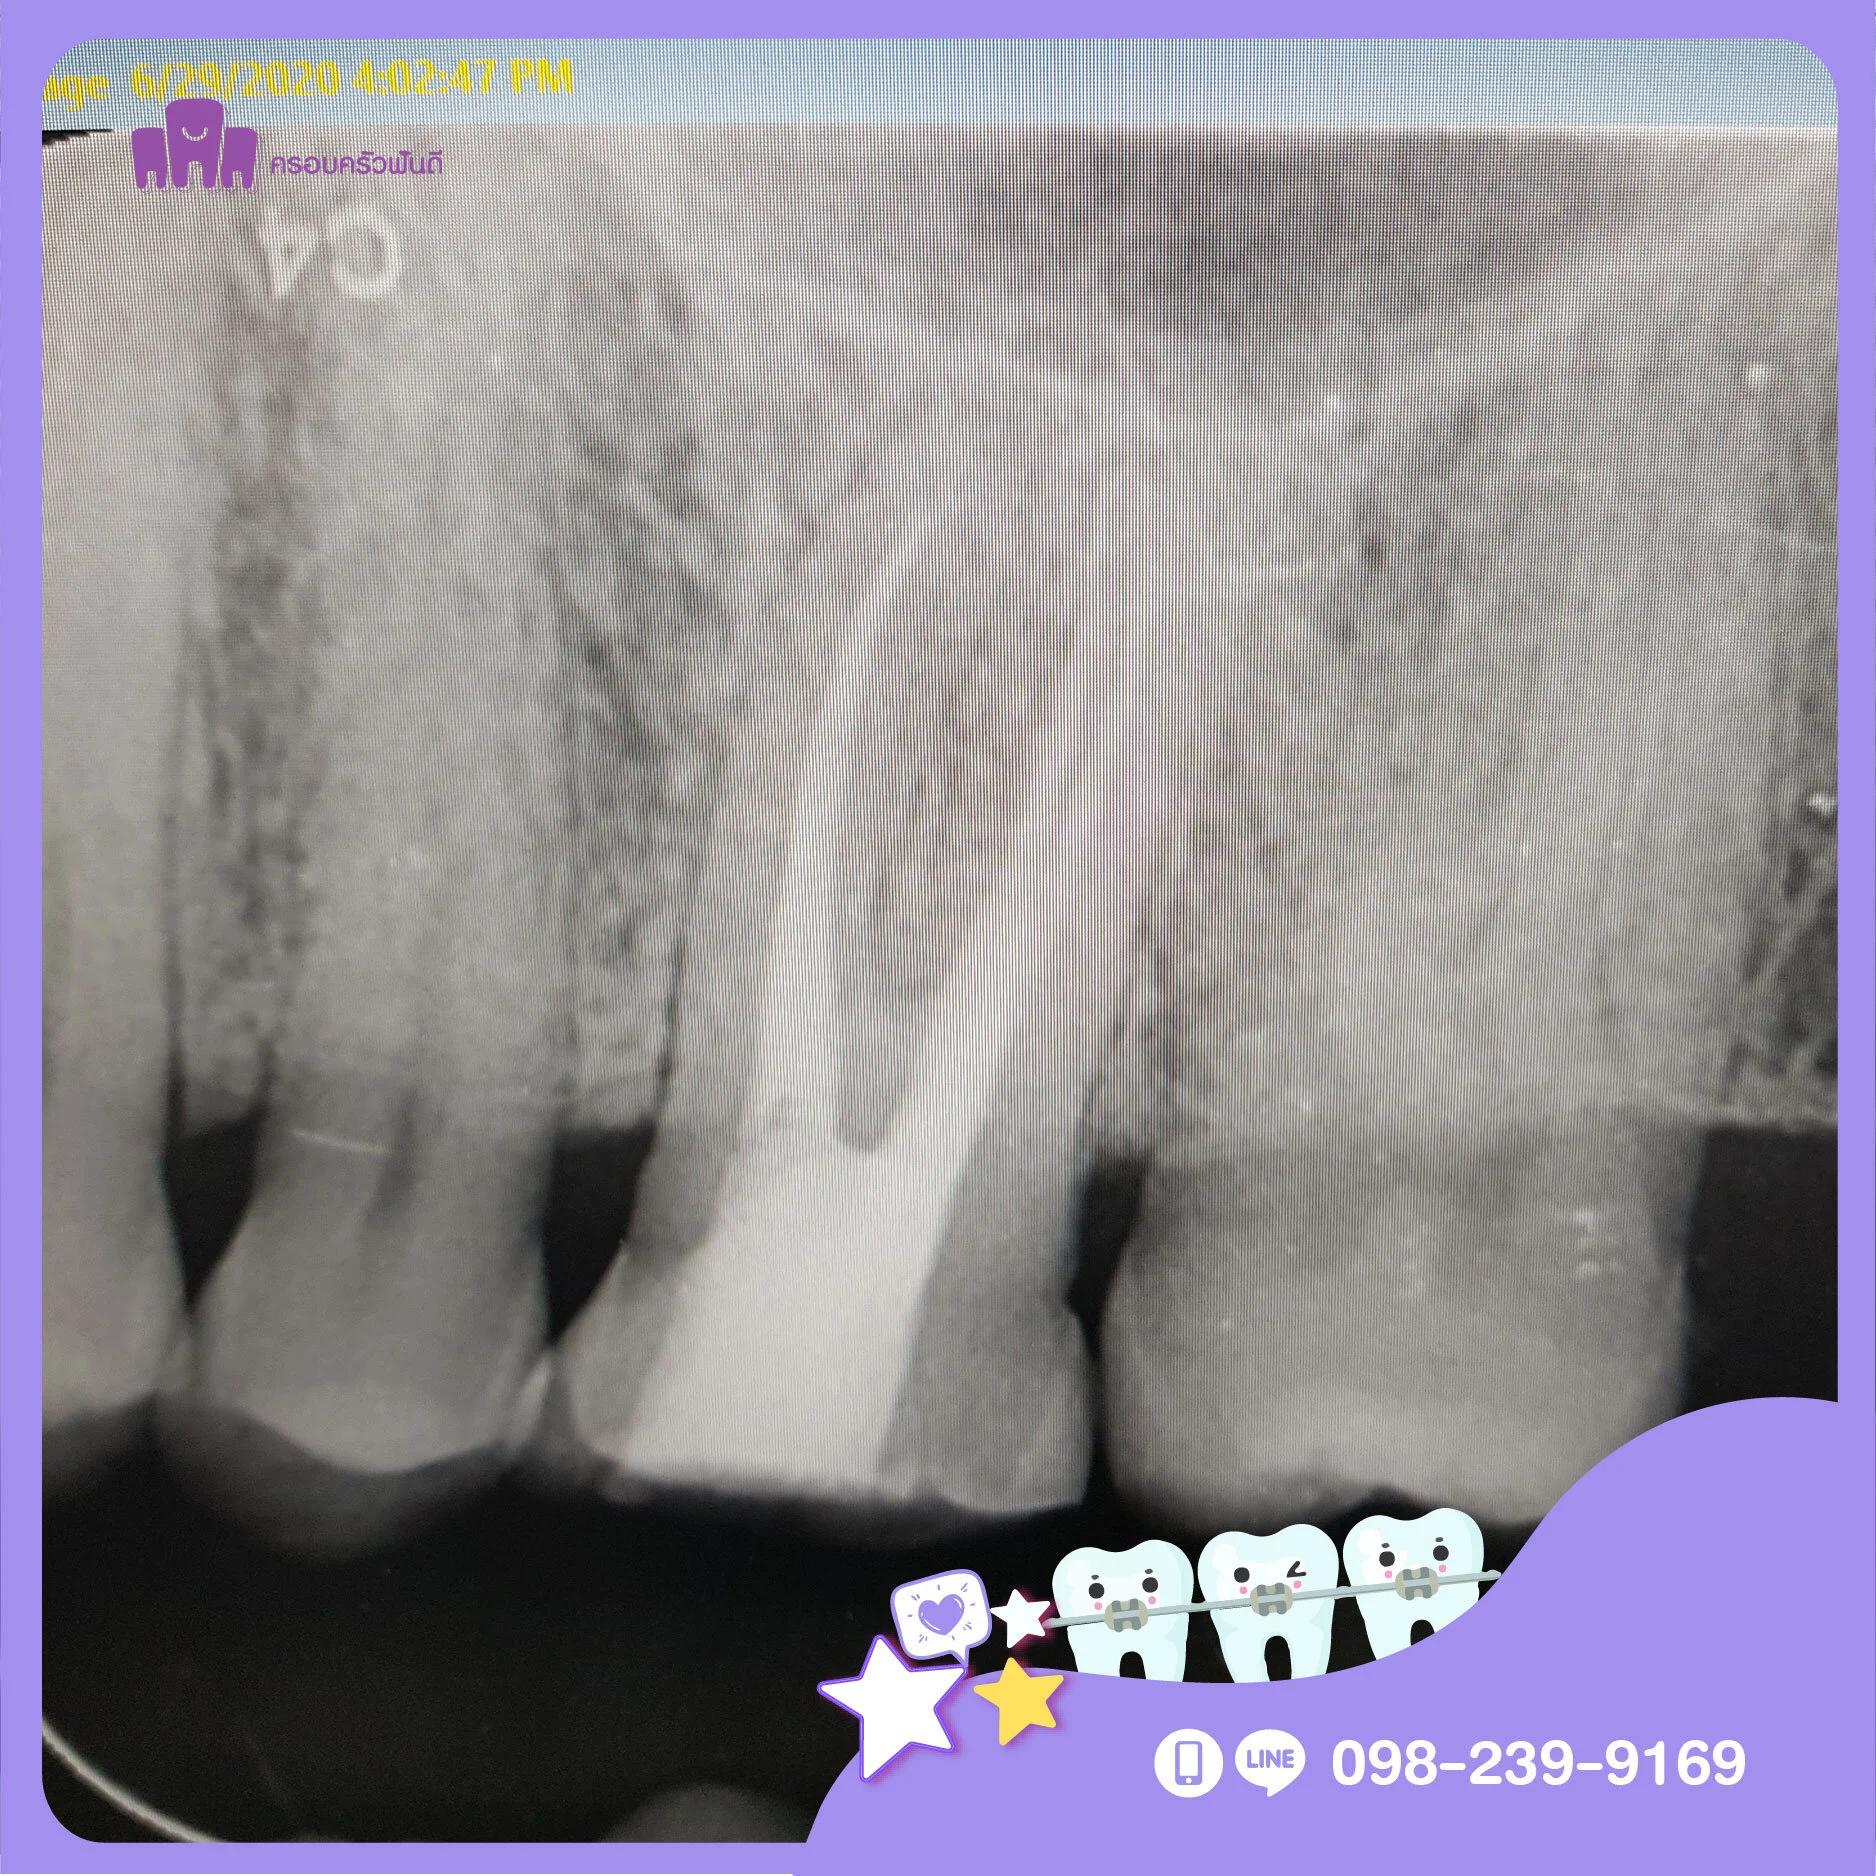

การปวดฟัน มีหลายแบบ เช่น อาการปวดฟันที่เล็กน้อย หรือปวดแบบรุนแรง จนบางครั้งรุนแรงจนนอนไม่หลับ อาจมีอาการปวดฟันโดยไม่มีสิ่งกระตุ้น หรือปวดเวลามีสิ่งกระตุ้นเช่นตอนเคี้ยวอาหาร บางกรณีมีเหงือกบวม หรือมีหนองซี่ที่ปวดร่วมด้วย รวมถึงการมีฟันสีคล้ำผิดจากฟันซี่อื่น และมีอาการเสียวฟันจากความเย็นหรือความร้อนซึ่งอาการเหล่านี้เป็นอาการเตือนในเบื้องต้นว่า มีการอักเสบของเนื้อเยื่อประสาทฟัน นอกจากนี้ยังมีบางกรณีที่ไม่มีอาการใดๆ เตือนให้รู้เลย มารู้ตัวอีกทีก็คือฟันโยกจนเกือบจะหลุด หรือฟันแตกหักรุนแรง เหลือแต่รากฟันเท่านั้น หากพบว่าตัวคุณมีอาการเหล่านี้ ควรปรึกษาทันตแพทย์ เพื่อตรวจ และเอ็กซ์เรย์ฟัน ซึ่งทันตแพทย์จะสามารถวินิจฉัยอาการของโรค และวางแผนการรักษาให้กับคุณได้

เพราะการปล่อยให้ฟันผุเป็นเวลานาน จนทำให้เกิดการอักเสบลึกเข้าไปใกล้โพรงประสาทฟัน ส่งผลให้เชื้อแบคทีเรียที่อยู่ในน้ำลายเข้าไปในโพรงประสาทฟันและทำอันตรายต่อประสาทฟันอย่างแรง หรือกรณีที่ฟันแตกหักที่เกิดจากอุบัตเหตุ ฟันถูกกระแทกอย่างแรง ก็อาจทำให้ส่วนปลายประสาทฟันตายได้ หากไม่ได้รักษาก็จะเกิดการอักเสบเป็นหนองที่รากฟันตามมา ทำให้เริ่มมีอาการปวดฟันซึ่งอาจจะปวดแบบเป็นๆ หายๆ หรือปวดเป็นระยะ ปวดอย่างรุนแรงจนกระทั่งนอนไม่หลับ โดยอาจจะมีอาการร่วมกับเหงือกบวมได้

การรักษารากฟัน บางกรณีสามารถรักษาให้เสร็จภายในครั้งเดียวได้ ทั้งนี้จะขึ้นอยู่กับสภาพของฟันว่ามีการอักเสบมากน้อยแค่ไหน ฟันที่รักษารากฟันแล้วควรได้รับการสังเกตุอาการไปอีกช่วงระยะเวลาหนึ่ง เพื่อให้แน่ใจว่าโรคที่เกิดขึ้นบริเวณปลายรากฟันหายดีเป็นปกติแล้ว บางคนอาจรู้สึกปวดฟันหรือเสียวฟันเล็กน้อยได้ใน 2-3 วันแรกหลังการรักษารากฟัน โดยทันตแพทย์จะให้ทานยาแก้ปวด ร่วมกับยาแก้อักเสบเพื่อบรรเทาอาการ ซึ่งอาการปวดนี้ก็จะค่อยๆ หายไปได้เอง แต่อาจจะต้องใช้เวลาสักระยะ หมั่นคอยดูแลทำความสะอาดช่องปากอย่างสม่ำเสมอ และงดใช้งานฟันซี่ที่ยังอยู่ในขั้นตอนการรักษา ห้ามเคี้ยวอาหารที่มีลักษณะเหนียวหรือแข็ง เพราะอาจจะทำให้ฟันแตกได้